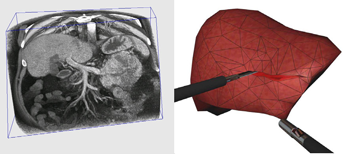

P. F. Villard, F. P. Vidal, L. ap Cenydd, R. Holbrey, S. Pisharody,

S. Johnson, A. Bulpitt, N. W. John, F. Bello, and D. Gould.

Interventional radiology virtual simulator for liver biopsy.

International Journal of Computer Assisted Radiology and

Surgery, 9(2):255-267, March 2014.

P. F. Villard, F. P. Vidal, L. ap Cenydd, R. Holbrey, S. Pisharody,

S. Johnson, A. Bulpitt, N. W. John, F. Bello, and D. Gould.

Interventional radiology virtual simulator for liver biopsy.

International Journal of Computer Assisted Radiology and

Surgery, 9(2):255-267, March 2014.

Purpose: Training in Interventional Radiology currently uses the apprenticeship model, where clinical and technical skills of invasive procedures are learnt during practice in patients. This apprenticeship training method is increasingly limited by regulatory restrictions on working hours, concerns over patient risk through trainees’ inexperience and the variable exposure to case mix and emergencies during training. To address this, we have developed a computer-based simulation of visceral needle puncture procedures. Methods: A real-time framework has been built that includes: segmentation, physically based modelling, haptics rendering, pseudo-ultrasound generation and the concept of a physical mannequin. It is the result of a close collaboration between different universities, involving computer scientists, clinicians, clinical engineers and occupational psychologists. Results: The technical implementation of the framework is a robust and real-time simulation environment combining a physical platform and an immersive computerized virtual environment. The face, content and construct validation have been previously assessed, showing the reliability and effectiveness of this framework, as well as its potential for teaching visceral needle puncture. Conclusion: A simulator for ultrasound-guided liver biopsy has been developed. It includes functionalities and metrics extracted from cognitive task analysis. This framework can be useful during training, particularly given the known difficulties in gaining significant practice of core skills in patients. Keywords: Biomedical computing, Image segmentation, Simulation, Virtual reality |